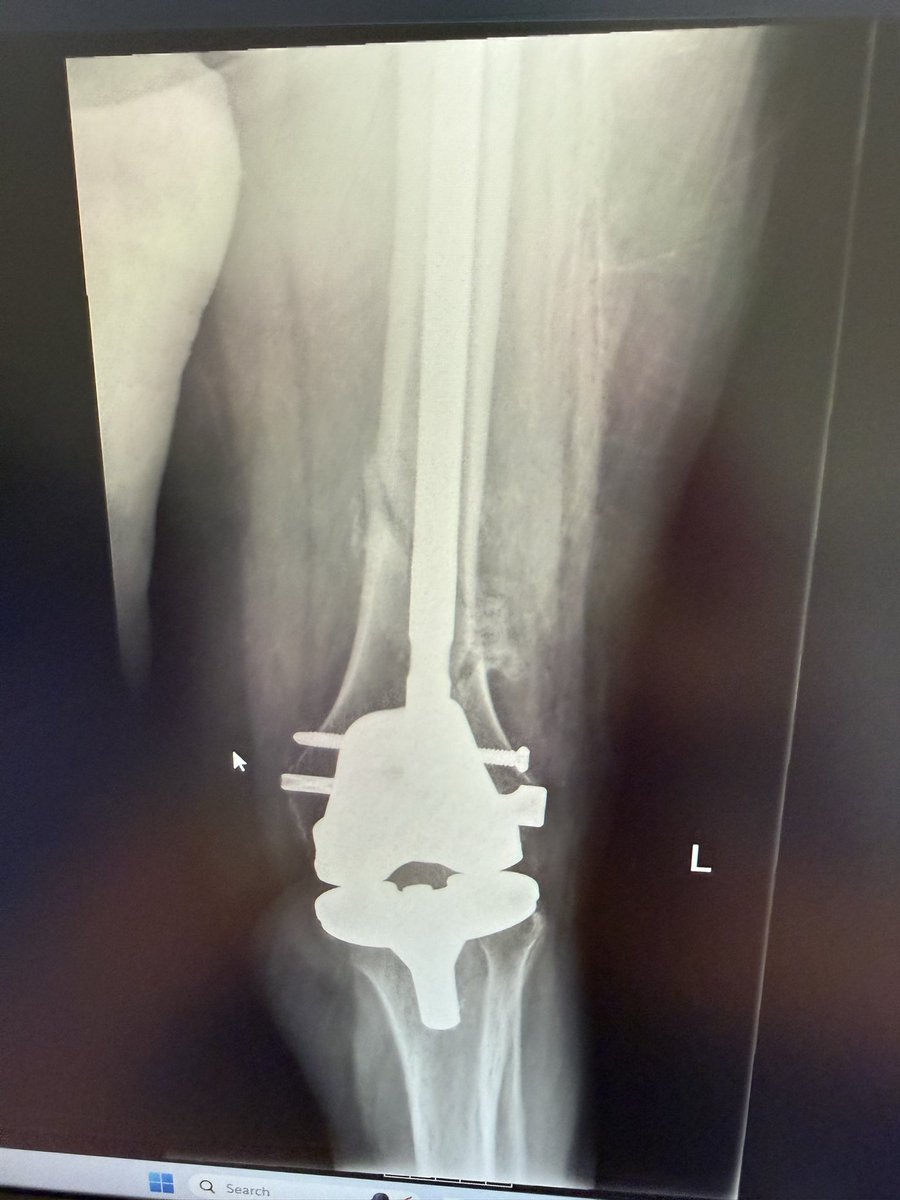

Can you answer our free question of the day? A patient presents to the trauma bay after involvement in a motor vehicle collision. Radiographs obtained in the trauma bay demonstrate a right distal femur fracture, as seen in Figure A. In surgery, the articular block is reduced, and reduction is held with headless compression screws. A retrograde intramedullary nail is then placed. After nail advancement, a varus and recurvatum deformity is noted at the fracture site with intraoperative fluoroscopy, as demonstrated via illustrations in Figures B and C. Placement of blocking screws in which locations (A - H) from Figure B and C would help correct this deformity? 1. B + E 2. A + G 3. B + F 4. C + H 5. D + H QID: 217509 Comment your answer below, then check to see if you got it correct by clicking the link below to see the answer & explanation. bit.ly/3OxP8sP #orthopedics #orthopedicsurgeon #orthopaedics #orthopaedic #orthopedic #ortholife #orthobullets #orthoresidents #orthoresident #orthoresidency #medicalschool #medicalstudent #medstudent #doctor